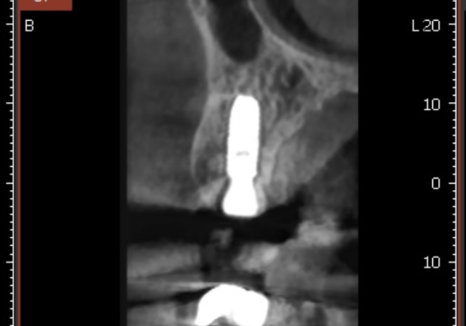

240202

그 후 4개월이 지나, 임플란트 뿌리와 뼈가

단단하게 굳은 것을 확인한 뒤,

지르코니아로 보철물을 올려드려

치료를 마무리했습니다.

240321